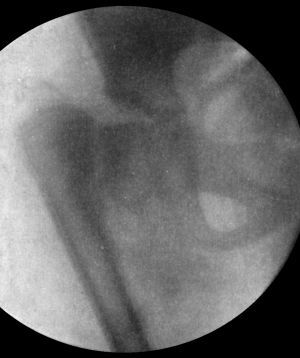

| 104. | Radiogram of Specimen of Arthropathy of Shoulder in Syringomyelia | 204 |

| 103. | Arthropathy of Shoulder in Syringomyelia | 203 |